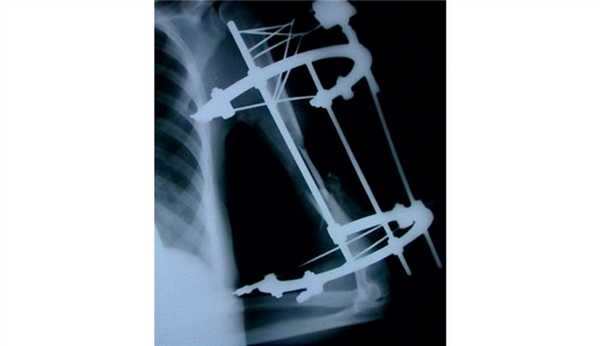

С 1998 по 2013 г. в клиниках травматологии и ортопедии Управления делами Президента РФ оперированы 55 пациентов с внутрисуставными оскольчатыми переломами мыщелков плечевой кости, которым был выполнен чрескостный остеосинтез аппаратом внешней фиксации конструкции А.И. Городниченко.

Хирургическое лечение переломов мыщелков плечевой кости осуществляли методом чрескостного остеосинтеза с применением спице-стержневого аппарата, основными преимуществами которого являлись стабильность достигаемого остеосинтеза на весь период лечения, элементы аппарата, изготовленные из высокопрочного рентгенопрозрачного углепластика, что позволяло контролировать точность закрытой репозиции во всех проекциях, одностороннее расположение, компактные размеры и незначительная масса всей конструкции, а также «плавающие» держатели стержней, не препятствующие устранению всех видов смещения костных отломков [2]. Наш опыт наглядно показал простоту и безопасность остеосинтеза данным аппаратом, минимальную травматичность операции и высокую стабильность фиксации костных отломков даже у больных с остеопорозом.

Показаниями к чрескостному остеосинтезу аппаратом внешней фиксации являлись открытые и закрытые оскольчатые внутрисуставные переломы мыщелков плечевой кости типов 13-С1,2,3 по классификации АО [4] (рис. 1). Рисунок 1. Классификация АО внутрисуставных оскольчатых переломов мыщелков плечевой кости (тип 13-С1,2,3). Среди повреждений преобладали открытые и закрытые переломы типов 13-C1,2 по классификации AO. В случае открытых повреждений подобного типа больные были оперированы в течение первых 6 ч с момента поступления. Переломы 13-С1 встречались в 26 (47,2%) наших наблюдениях, переломы 13-С2 - в 20 (36,4%) и переломы 13-С3 - в 9 (16,4%) наблюдениях.

Все оперативные вмешательства проводили на ортопедическом столе под контролем электронно-оптического преобразователя. Методом анестезии являлась либо проводниковая анестезия - блок плечевого сплетения, либо внутривенный наркоз. Репозицию перелома, как правило, проводили закрыто, и только при многооскольчатых внутрисуставных переломах типа 13-С3 выполняли открытую репозицию с целью наиболее точного восстановления конгруэнтности суставных поверхностей. Количество вводимых стержней зависело от характера перелома и наличия сопутствующего остеопороза. В область дистального метаэпифиза плечевой кости вводили 1 или 2 стержня и 1 или 2 спицы с упорными площадками, которые крепили с наружной стороны в аппарате внешней фиксации. В диафиз плечевой кости вводили 1 или 2 кортикальных стержня. Все стержни вводили через разрезы кожи длиной до 5 мм, что позволяло сократить интраоперационную кровопотерю до 10-30 мл, а продолжительность операции до 30-45 мин. Окончательной репозиции достигали на операционном столе с помощью средств ручной репозиции, чему в значительной мере способствовало то обстоятельство, что основные элементы аппарата были выполнены из рентгенопрозрачного углепластика.

На следующий день под новокаиновым блоком плечевого сплетения произведена операция: закрытая репозиция и чрескостный остеосинтез левой плечевой кости спице-стержневым аппаратом внешней фиксации конструкции А.И. Городниченко. Через разрезы кожи и мягких тканей по наружной поверхности левого плеча длиной до 5 мм введено 2 кортикальных стержня в диафиз плечевой кости, один кортикальный и один спонгиозный стержень и 2 спицы с упорной площадкой в мыщелки и надмыщелки плечевой кости. После фиксации проксимальных стержней в аппарате под контролем электронно-оптического преобразователя произведена закрытая репозиция с помощью съемных рукояток с последующей стабилизацией дистальных стержней и спиц (рис. 3). Рисунок 3. Рентгенограммы больной П. после остеосинтеза левой плечевой кости спице-стержневым аппаратом. Кожа вокруг стержней ушита одиночными швами. Кровопотеря в ходе операции 20 мл. Продолжительность операции 40 мин.